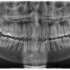

Xray of my fully horizontal wisdom teeth. Submitted by kasuma9999 t3_10prqtx on January 31, 2023 at 7:24 AM in mildlyinteresting 45 comments 113